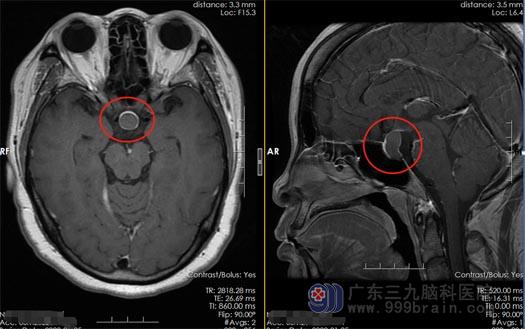

黄女士因为左眼视力下降,被广东三九脑科医院神经外五科诊断为“颅内鞍区占位”,需要手术治疗。

完善相关检查与术前准备以后,黄女士接受了神经外五科治疗团队施行的“内镜经鼻蝶鞍区占位病变切除术”,手术很顺利,肿瘤被完整的去除了。术后的黄女士视力得到明显的改善。

▲术前